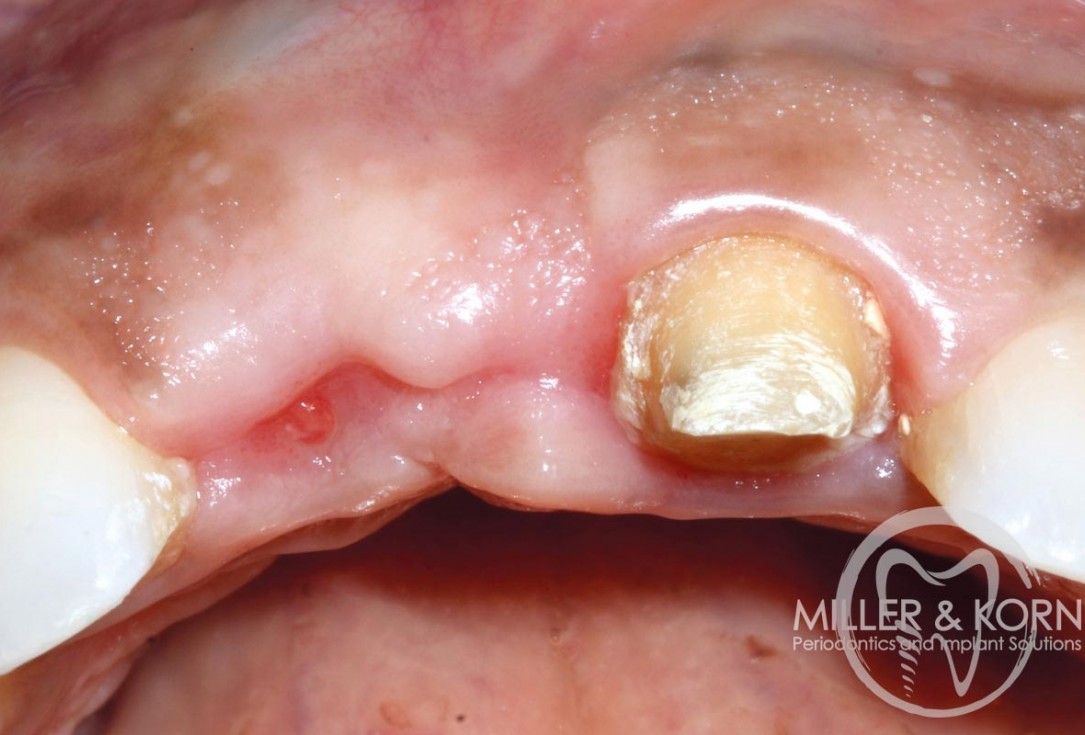

4/22 - Full thickness flap elevation with vertical releasing incisions. Note, significant apical and buccal bone resorption after raising the flapImmediate implant placement and regeneration of ridge using an allograft bone ring and Jason® membrane - Drs. Miller and Korn

18/22 - Placement of healing abutment. Note buccal convexityImmediate implant placement and regeneration of ridge using an allograft bone ring and Jason® membrane - Drs. Miller and Korn